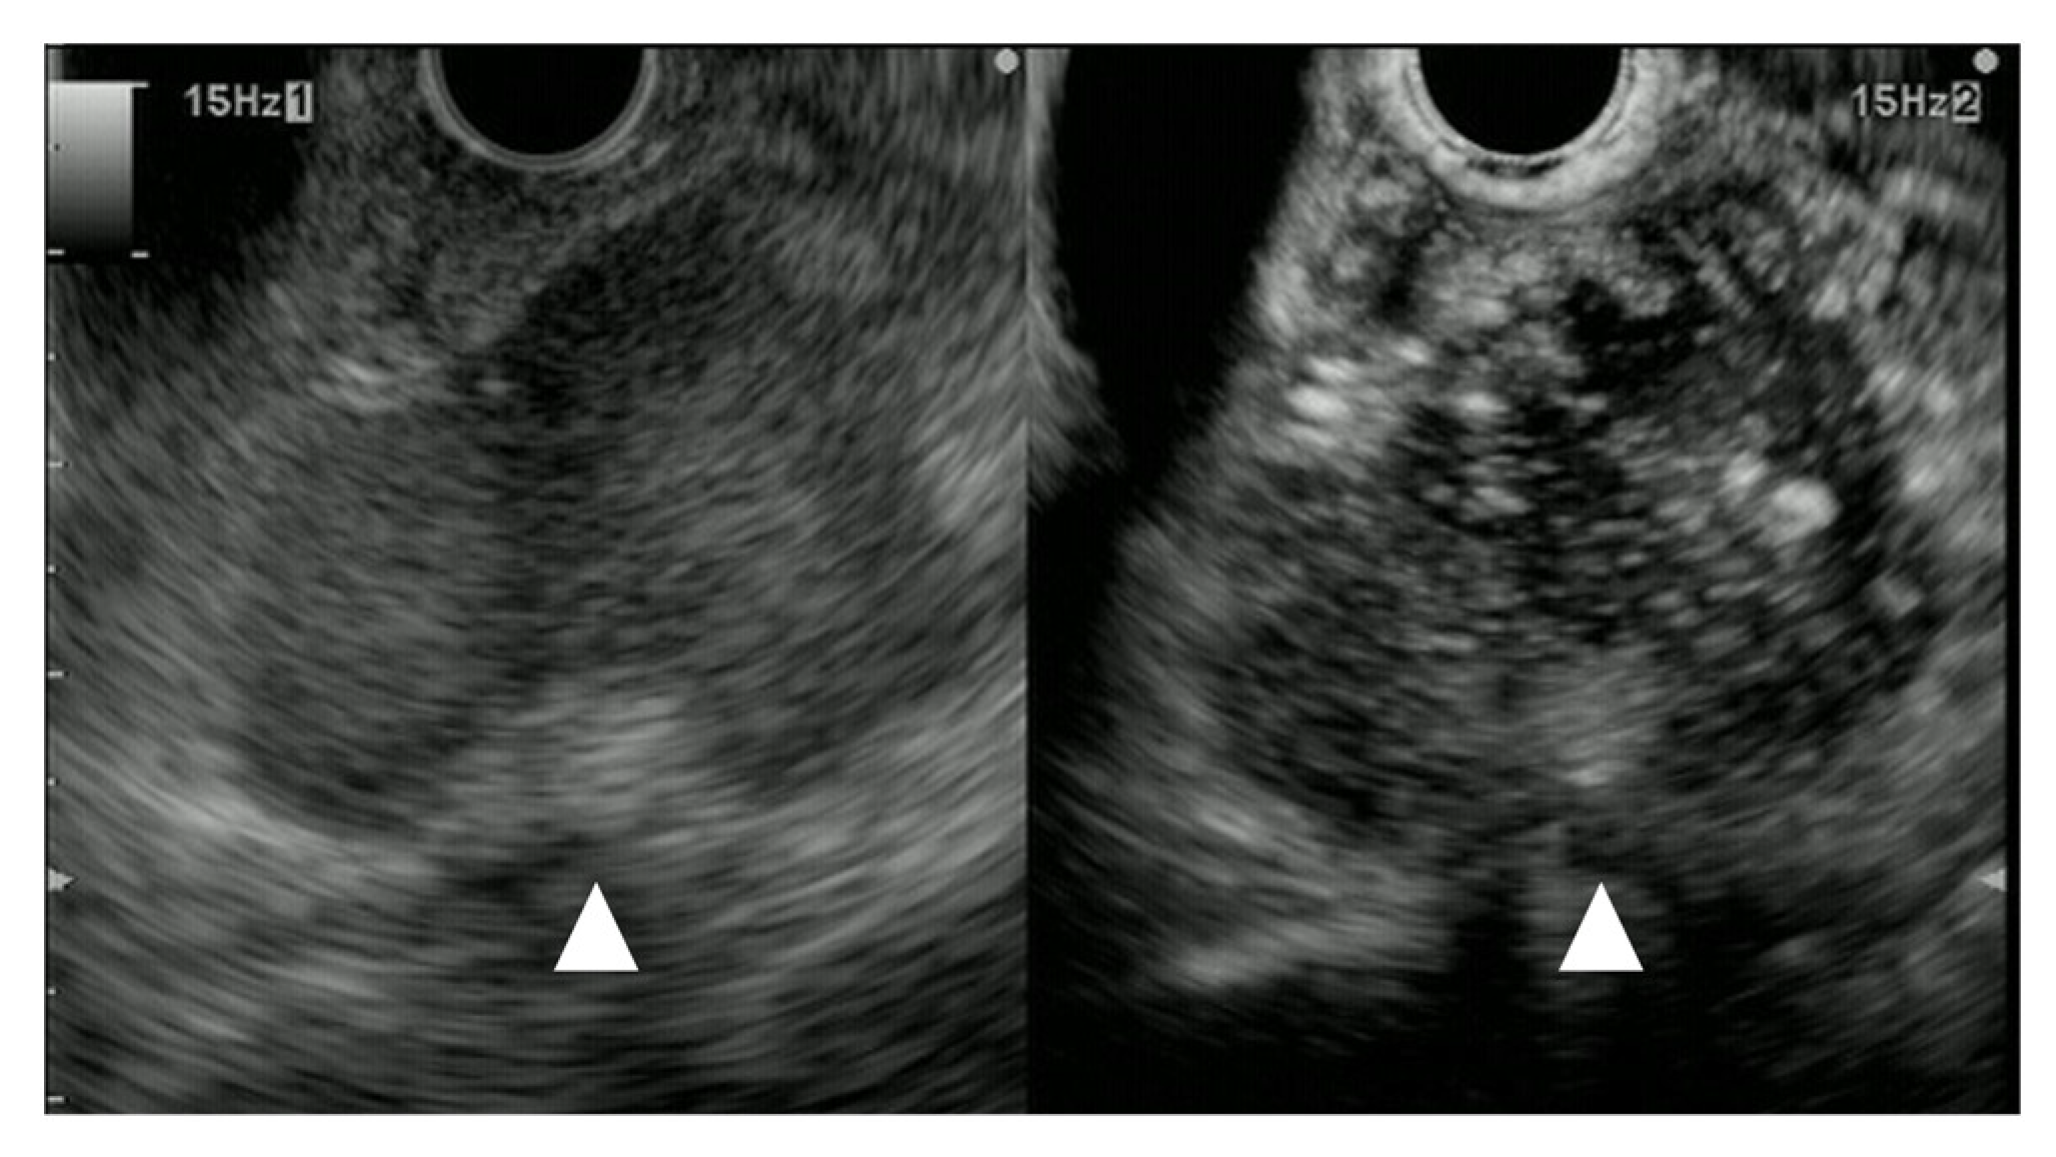

B-mode US/EUS

| Mostly hypoechoic, homogeneous, or heterogeneous More likely well-defined borders (46%) Anechoic and hyperechoic lesions are possible | Hypoechoic, typically heterogeneous, irregular borders | Hypoechoic, mostly homogeneous, smoothly bordered. Cystic components or cystic solid PanNENs are possible |

| Variable, in 80% no pancreatic duct dilatation | Pancreatic duct stenosis and pancreatic duct dilatation are an early and typical feature | No pancreatic duct dilatation |

| Mostly no infiltration into adjacent vessels | Infiltration around and into the vessels | No infiltration into adjacent vessels |

| Colour Doppler Imaging | RCC metastases are hypervascularized Most other pancreatic metastases are hypovascularized | No hypervascularization | Hypervascularized |